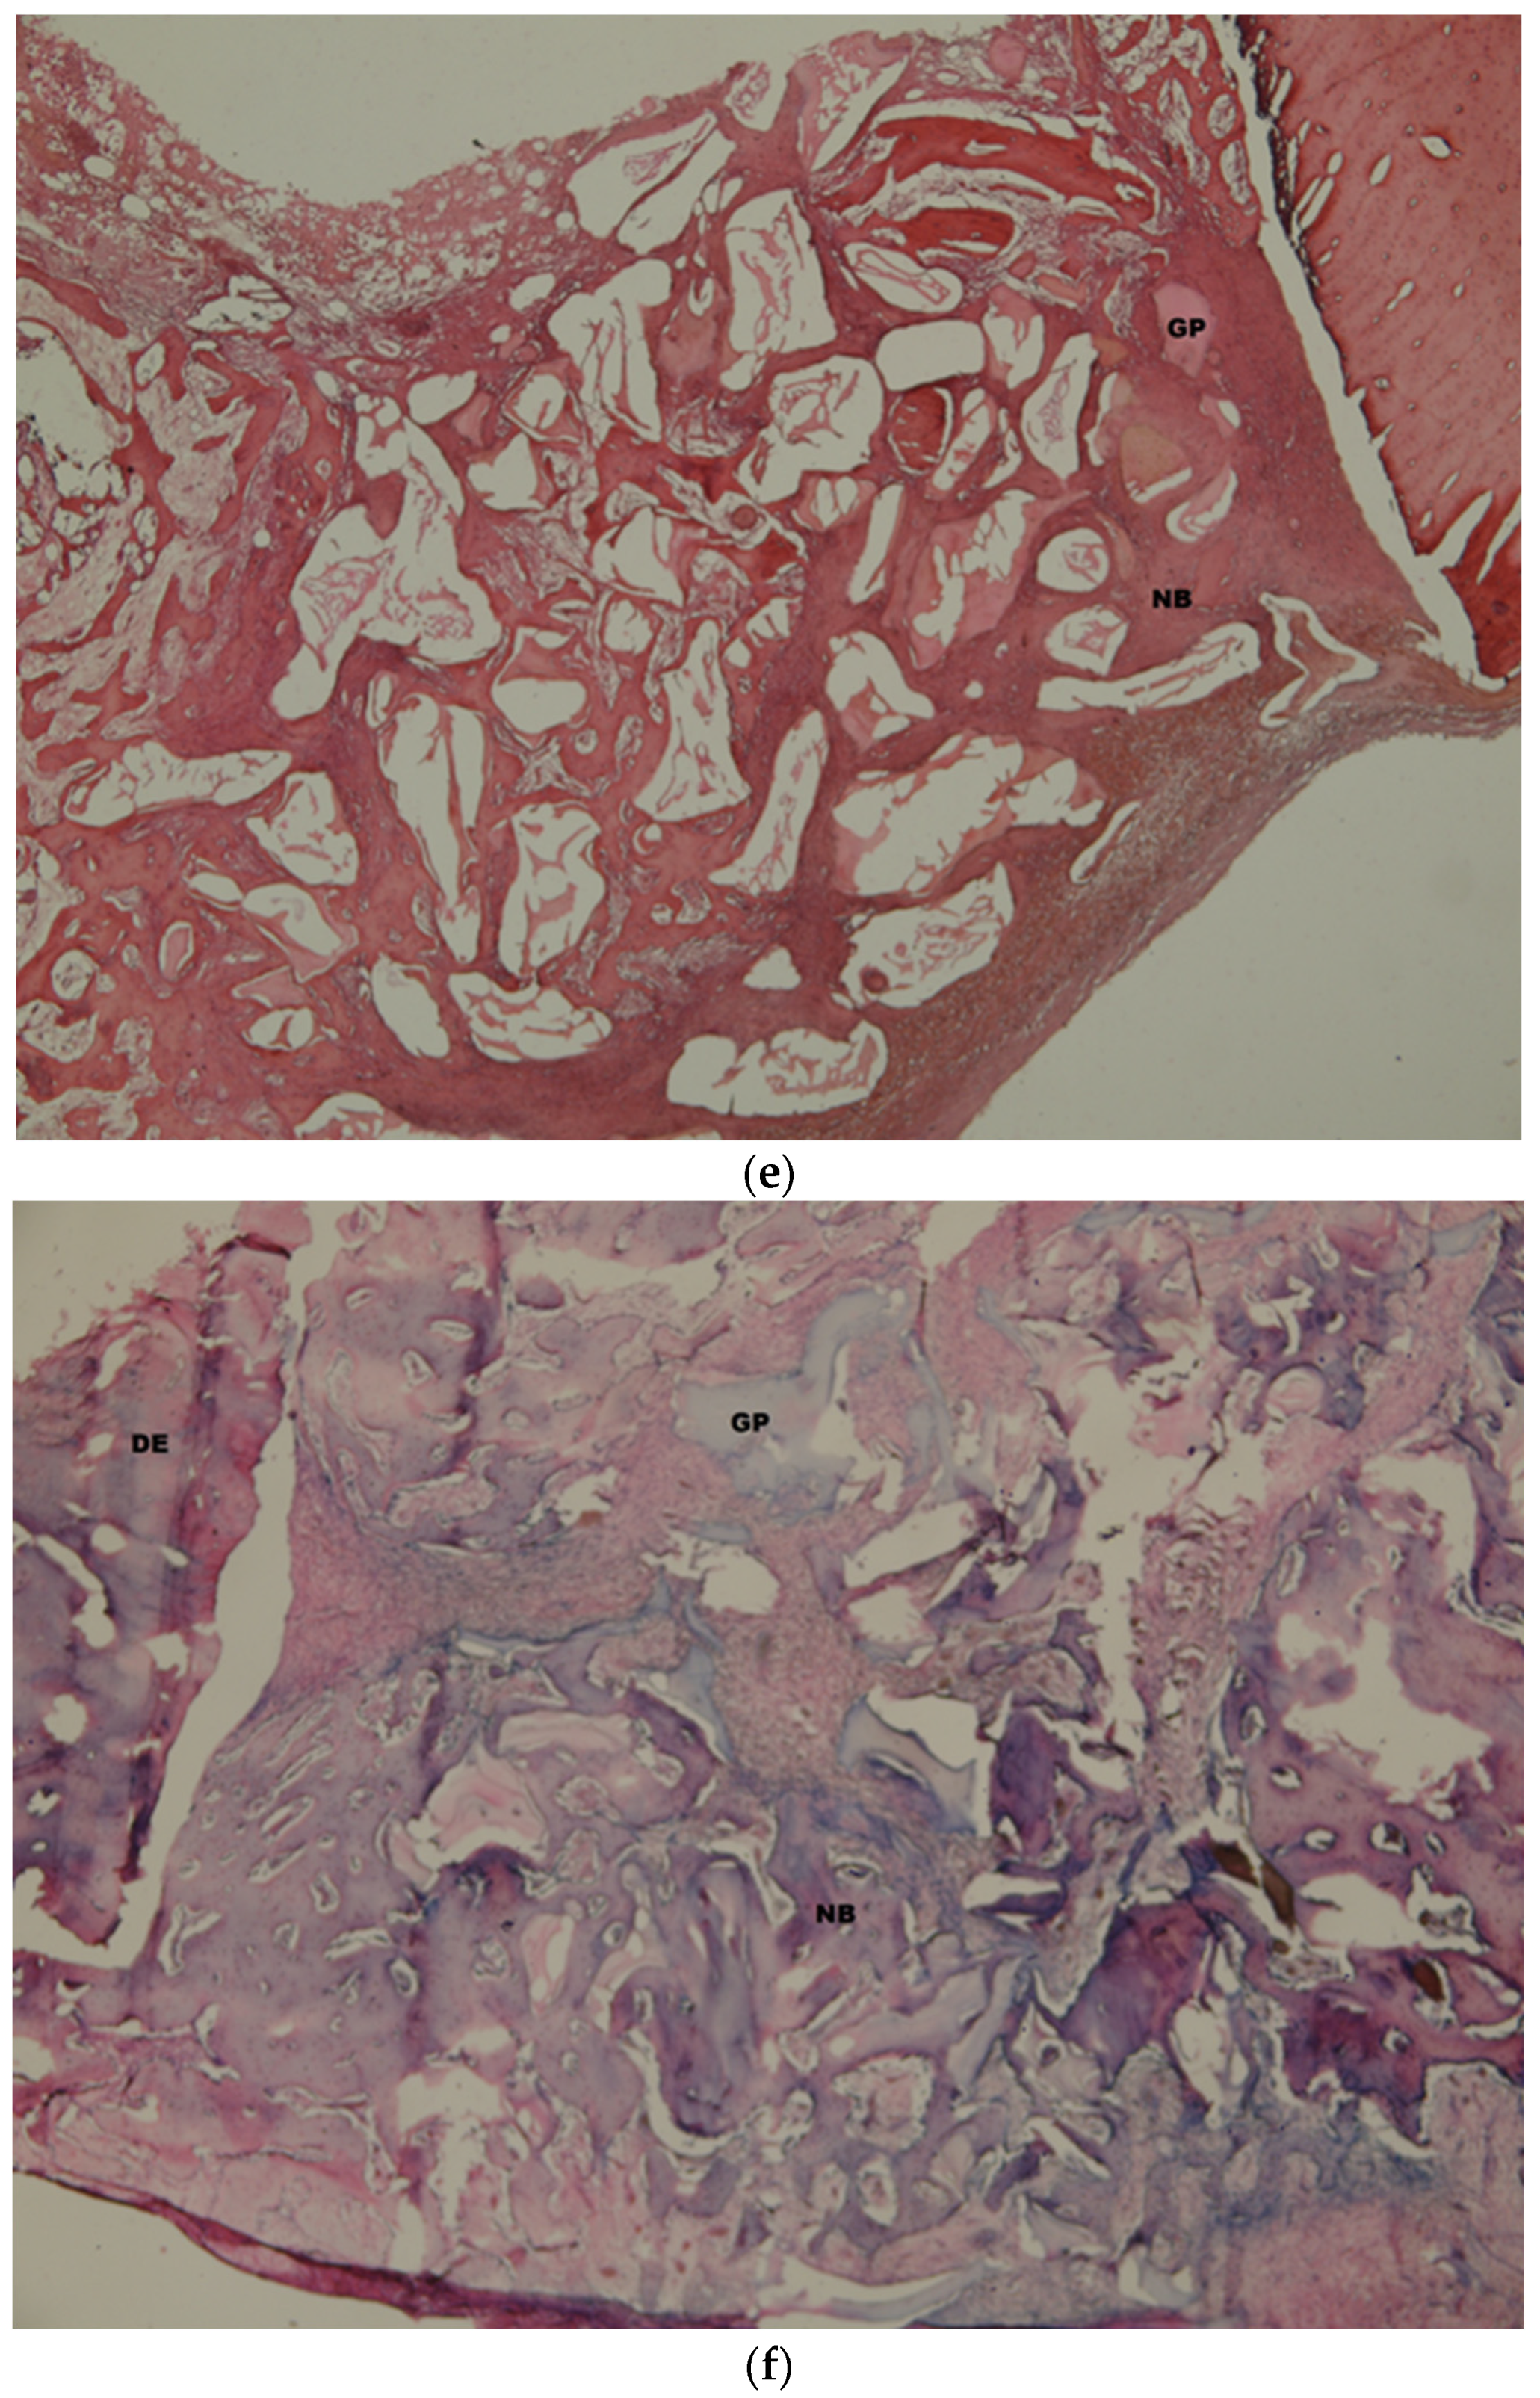

3.2. Histologic and Histomorphometric Findings